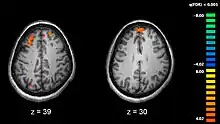

FMRI showing the active areas of a schizophrenic participant's brain while performing working memory tasks

Confabulation is the involuntary false remembering of events and can be a characteristic of several psychological diseases such as Korsakoff's syndrome, Alzheimer's disease, schizophrenia and traumatic injury of certain brain structures.[36] Those confabulating don't know that what they are remembering is false and have no intent to deceive.[37]

In the regular process of reconstruction, several sources are used to accrue information and add detail to memory. For patients producing confabulations, some key sources of information are missing and so other sources are used to produce a cohesive, internally consistent, and often believable false memory.[38] The source and type of confabulations differ for each type of disease or area of traumatic damage.